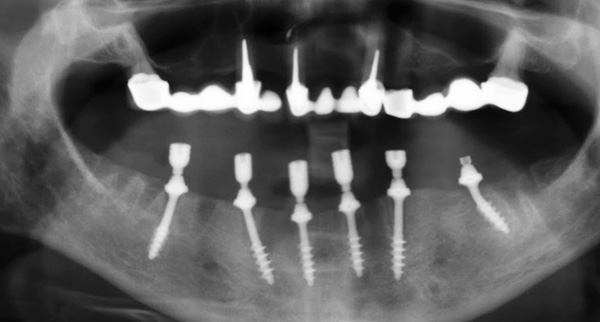

Tipos de implantes e características de sua instalação

A técnica de prótese dentária All-on-4 utiliza implantes de dois componentes com construção de parafuso - esses são, de fato, modelos clássicos em forma de raiz feitos de titânio puro e equipados com um revestimento TiUnite poroso especial (presente em todos os modelos de implantes desta marca). É uma camada rugosa de óxido de titânio com alto teor de fósforo, que acelera significativamente o processo de osseointegração, ou seja, fusão de ossos e implantes.

Esses implantes também são instalados da maneira tradicional (retalhos) - após a introdução da anestesia, a gengiva é cortada, esfoliada do tecido ósseo, uma cama sob o implante é formada dentro do osso (cortada com boro) e, após a colocação do implante, a gengiva é suturada.

O conceito implica o uso de apenas 4 implantes (com a abordagem clássica, eles exigem pelo menos 8 a 10 por linha). Dois estão ligados na região dos dentes anteriores, os outros dois na região lateral. E eles são fixados em um ângulo de até 45º.

A instalação inclinada de implantes laterais possibilita sua implantação, contornando estruturas anatômicas importantes, por exemplo, nervos da mandíbula, seios da face. Além disso, é possível colocar os implantes de maneira mais uniforme ao longo da crista alveolar e distribuir de maneira ideal a carga sobre eles. A inclinação dos “parafusos” laterais também permite aumentar a área de contato entre o implante e o osso, o que cria um suporte completo para a prótese.

O pilar é fixado na parte superior do implante. Para implantes inclinados, os pilares inclinados (unidades múltiplas) também são selecionados. Por esse motivo, a posição das pontas dos implantes acima da gengiva é nivelada e a prótese é fixada estritamente diretamente, sem perturbar a oclusão e oclusão do paciente.

Quando próteses usando o método All-on-6, modelos de implantes fundamentalmente diferentes são usados em comparação com a tecnologia All-on-4:

- Os implantes são de um componente, ou seja, o pilar e a parte intraóssea são um todo. Após a instalação, o pilar é inclinado para alinhar a mordida e a posição da prótese;

- Os implantes são fixados de maneira minimamente invasiva - são literalmente aparafusados no osso, enquanto a gengiva não esfolia, as suturas após a cirurgia não se sobrepõem. Isso significa que o paciente se recupera mais rapidamente;

- Os implantes são colocados em ângulo. Assim como na aplicação da tecnologia all-in-four, essa abordagem permite ignorar as seções mais atrofiadas do osso, escolhendo as seções mais fortes, e também não prejudicar os nervos e seios.